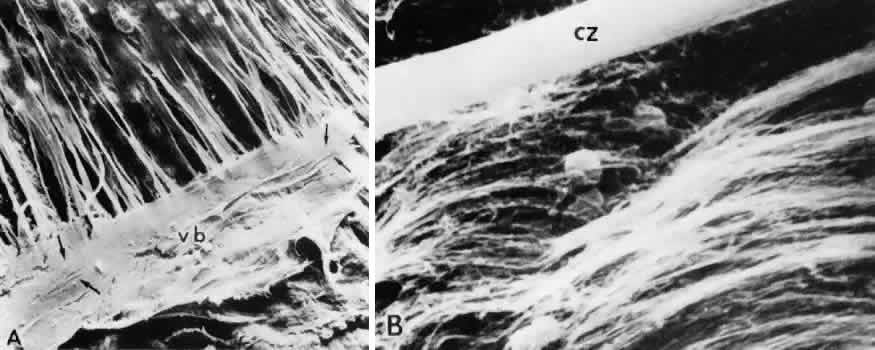

The posterior girdle of zonular bundles lies within the vitreous just above the main zonular stream 1 to 2 mm anterior to the ora serrata (Fig. 18). This is also the area in which the median vitreous tract inserts, to use Eisner's terminology.60 Vitreous collagen fibrils in the immediate vicinity of the zonular girdle fibers have a similar circumferential orientation. This suggests that the orientation of both types of fibers may be a response to the same mechanical stresses, such as vitreous traction during ocular movement and accommodative excursions.

Fig. 18. Posterior girdle zonules on the pars plana in the vitreous base. A. Arrows indicate fibers passing circumferentially in vitreous base remnants (vb) on the pars plana. Ciliary processes and minor plicae are on the upper left (SEM, × 65). B. High-power view of above area, showing 1.5-μm circumferential zonular bundle (cz) among the collagen fibers of the cortical vitreous that are also oriented circumferentially. Round particles are melanin granules (SEM, × 9,000).